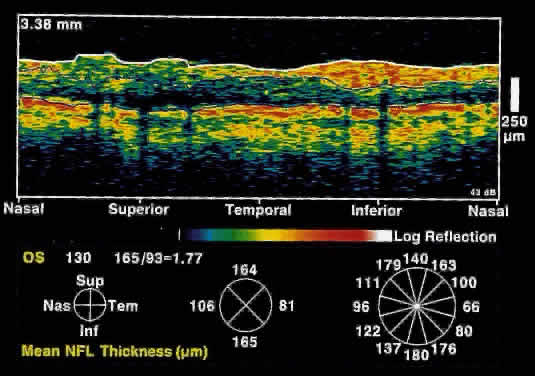

GLAUCOMA The diagnosis and management of glaucoma remains a difficult clinical problem. Intraocular pressure measurements do not always adequately predict the extent of glaucomatous change. Optic nerve head and gonioscopic evaluation by slit-lamp biomicroscopy is subjective. Visual field loss and optic nerve head cupping are late clinical findings, detected only after up to 50% of retinal nerve fibers have been lost. OCT, because of its high resolution, is able to detect nerve fiber layer thinning before the onset of visual changes.21 Nerve fiber layer thickness, as measured by OCT, has been shown to correspond to visual function. As expected from the histology of the peripapillary retina, the nerve fiber layer is thickest in the inferior and superior quadrants. The nerve fiber layer has been demonstrated to be significantly thinned in areas corresponding to visual field loss. Typically, the scans are performed radially around the optic nerve for 360° using two radii of curvature (2.25 and 3.37 mm), and the nerve fiber layer thickness is plotted schematically (Fig. 16). Normal nerve fiber layer thickness is a mean of 148.6 microns for superior nerve fibers, 143.5 microns for inferior nerve fibers, 66.9 microns for temporal nerve fibers, and 117.2 for nasal nerve fibers. The direct measurement of the nerve fiber layer thickness by OCT is an objective assessment of glaucomatous progression. OCT shows promise in the early diagnosis of glaucoma before visual field defects, optic nerve head changes, and ophthalmoscopically visible nerve fiber layer loss are evident.